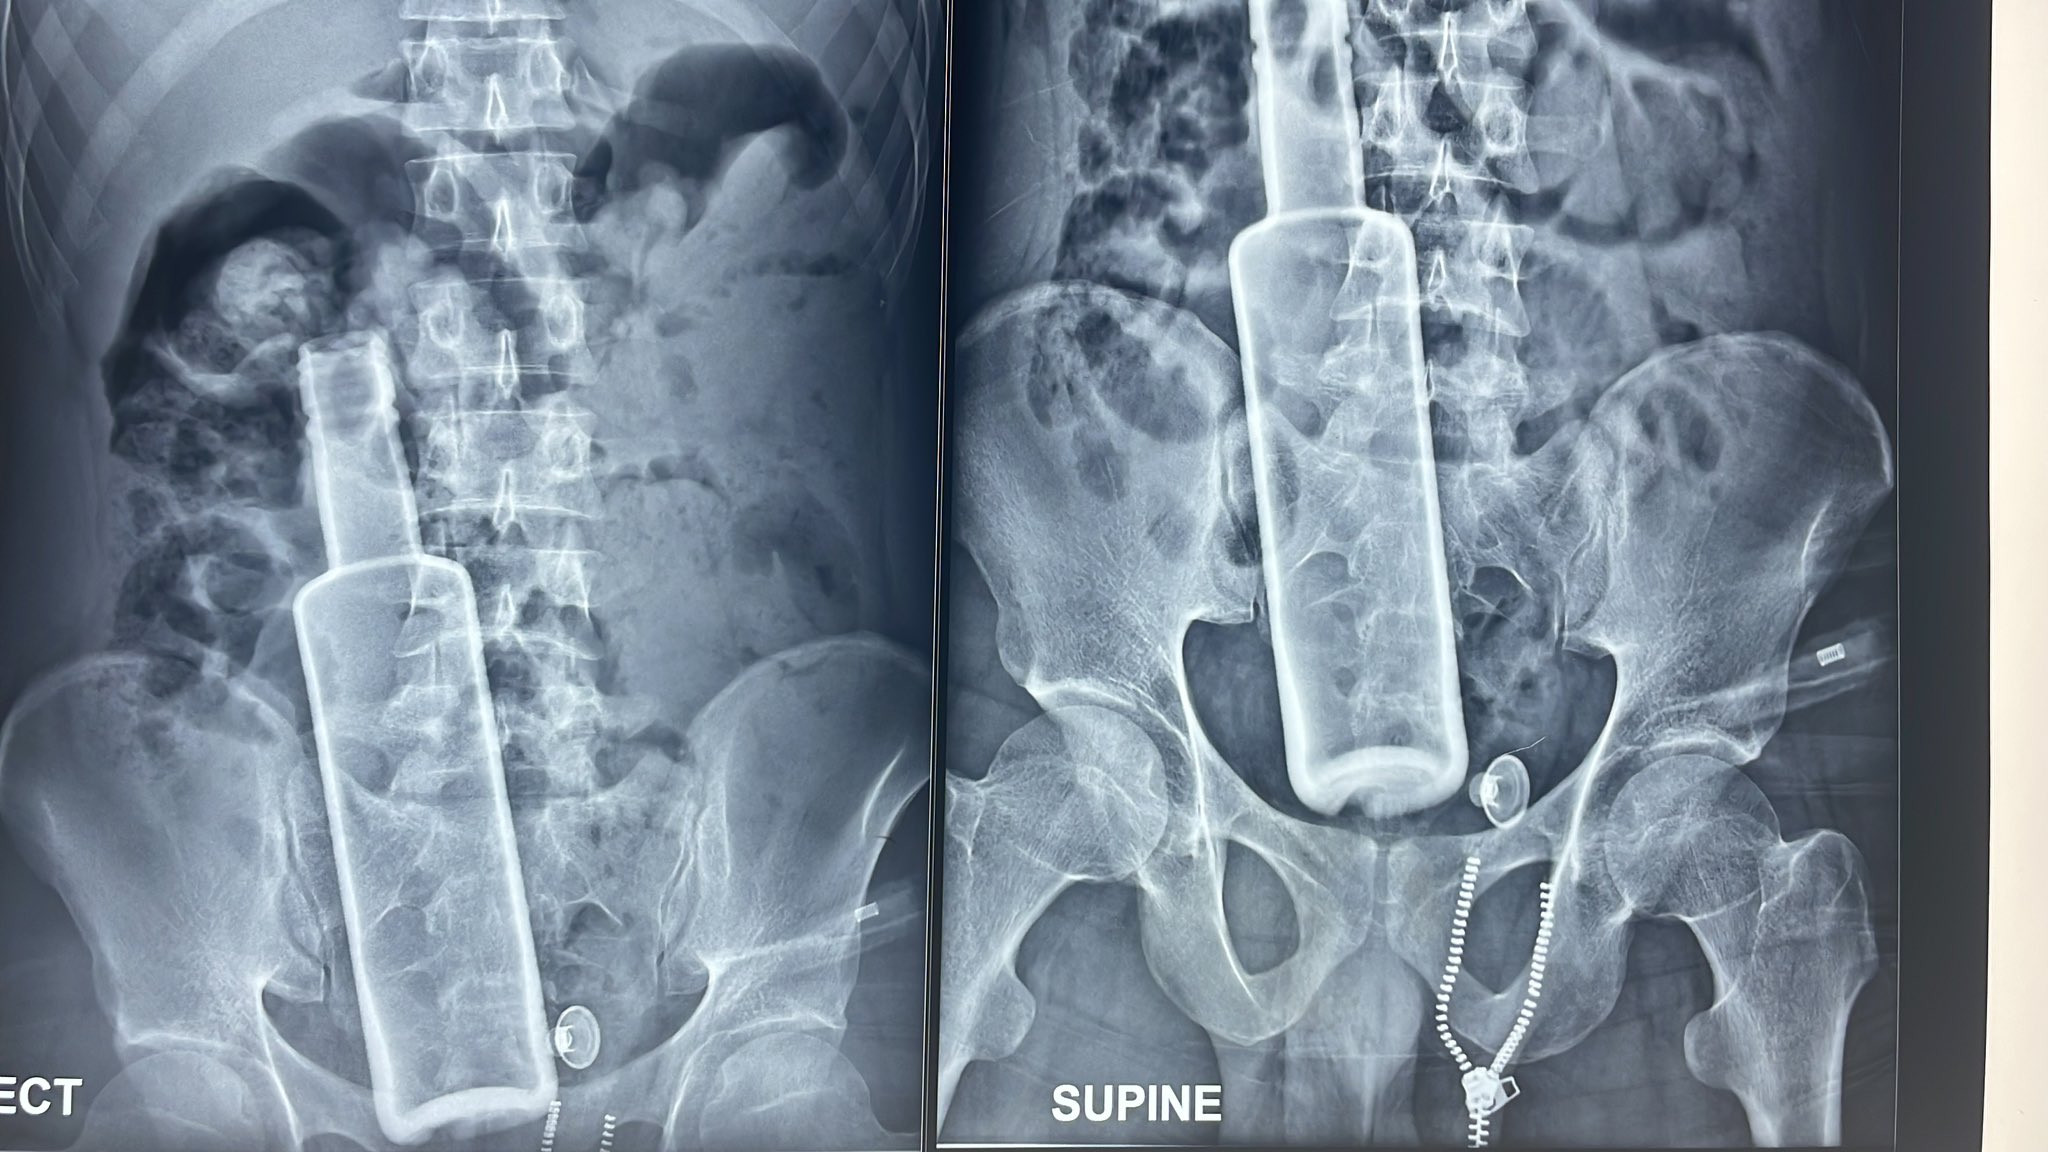

रौतहटको चन्द्रनिगाहपुरबाट ल्याइएका बिरामीको नाडीको चाल १२० भन्दा माथि पुगेको थियो। पेट फुलेर ठूलो भएको थियो। बिरामीसँग आएका व्यक्तिको साथमा रहेको एक्सरे रिपोर्ट डाक्टरलाई नै तर्साउने खालको थियो।

एक्सरेमा उनको पेटमा एउटा सिंगो बोतल देखिन्थ्यो।

बिहान साढे ६ बजेतिरबाट बिरामीको शल्यक्रिया सुरू गरिएको थियो। बोतलको आधा भाग पेटभित्र र आधा भाग ठूलो आन्द्राभित्रै रहेको देखियो। बोतलको टुप्पो आन्द्रा फुटालेर बाहिर निस्किएको थियो। पेटभित्र दिसा फैलिएर आन्द्राहरू सबै सुन्निइसकेका थिए। बोतलमा बिर्को थिएन। भित्र केही दिसा र रगत पसेको थियो।

शल्यक्रिया गरेर बिरामीको पेटबाट निकालिएको बोतल। तस्बिर: राजेश घिमिरे/सेतोपाटी